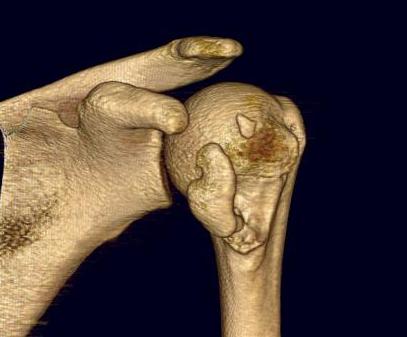

proximal humerus fracture Background ORIF with locking plate Arthroplasty Greater tuberosity fractures Lesser tuberosity fractures / avulsions Book traversal links for Proximal humerus fractures ‹ Pectoralis Major Tears Up Background ›